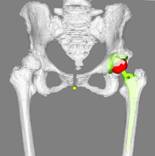

(3)-Ⅰ: 臼蓋カップの設置

矢状断面での傾斜を加味した機能的骨盤基準面(FPP:functional pelvic plane)に対して骨性被覆・大腿側も加味した脚長を考慮しカップを設置

(3)-Ⅱ: ステムの設置

前捻角を後顆接線に対して任意に設定し、髄腔との適合性・オフセット・脚長を考慮しながらステムを設置

(4) 可動域シミュレーションにて確認

予定引下げ距離・術後全体像をイメージ・インプラント・骨性インピンジメントの確認をし終了術前計画に要する時間: 約20分